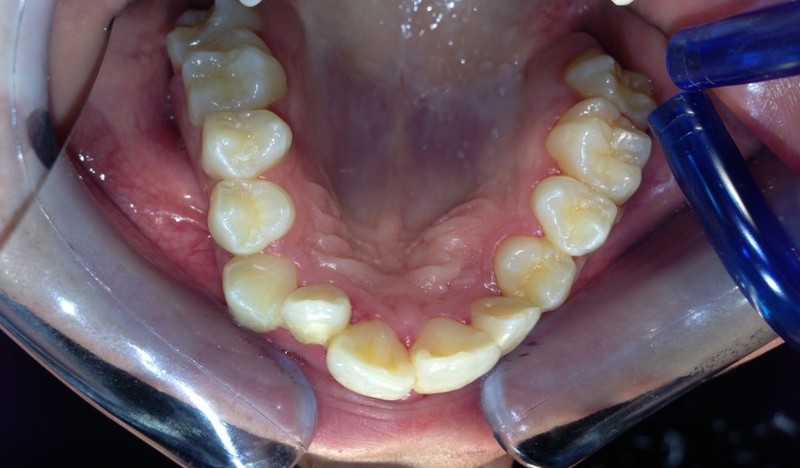

Paziente candidato a intervento di chirurgia Ortognatica